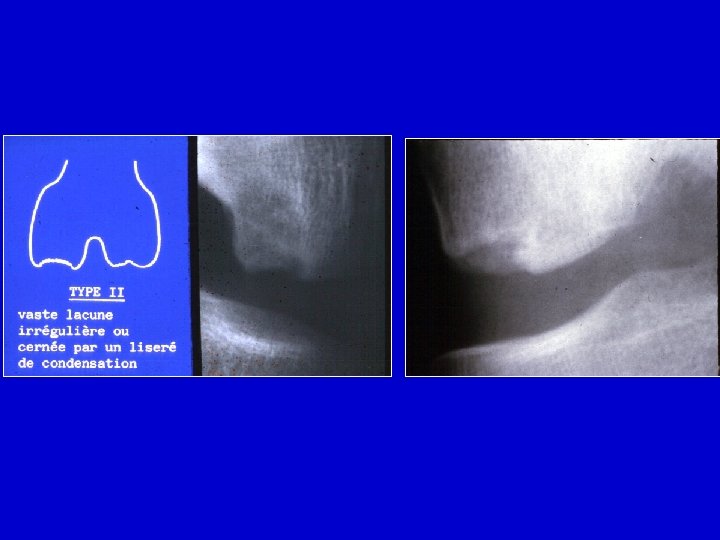

Radiografie • All’inizio la zona di necrosi appare condensata Le cartilagine é intatta • Più tardi il frammento si può separare dall’osso vicino • Le cartilagine può restare intatta • Il frammento può staccarsi e migrare nell’articolazione

Radiografie semplici

I : Cartilagine II : osso necrotico separato III: tessuto fibroso IV : zona necrotica V : Osso normale

Determinare la largezza e la profondità della zona necrotica